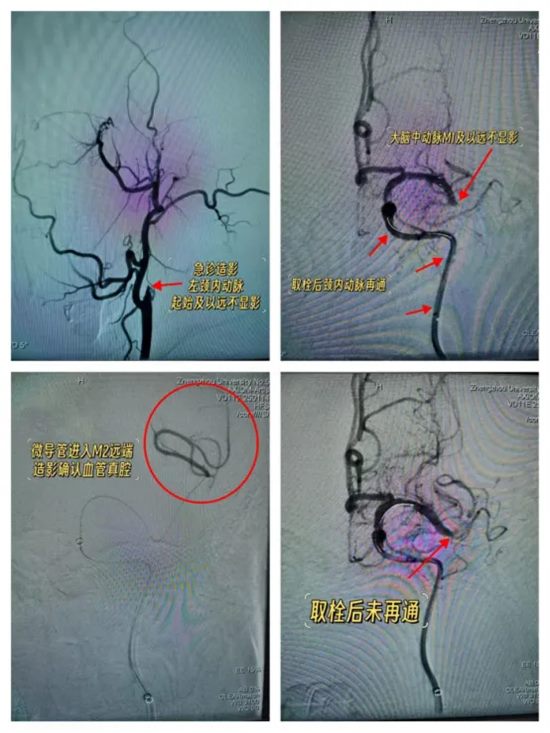

马建主任、周少龙副主任带领神经外科三病区脑血管病介入团队,率先为患者实施脑血管造影。结果清晰显示:患者左侧颈内动脉及大脑中动脉闭塞。

结合造影图像及患者病情,考虑为颈内动脉串联闭塞——这是急性缺血性脑卒中当中较为复杂、极具挑战性的亚型,治疗难度大、风险高,对术者的技术水平和决策能力提出了极高要求。

团队临危不乱,马建主任、周少龙副主任凭借丰富的临床经验和精湛的介入技术,当即决定采用支架取栓+负压抽栓相结合、球囊穿梭等技术,精准操作、稳步推进。

经过35分钟的紧张奋战,手术取得阶段性成功——首次开通患者左侧颈内动脉,脑血管造影显示颈内动脉血流通畅!

然而,大脑中动脉M1末端及以远仍不显影。团队尝试开通,支架+负压抽吸取栓后造影——大脑中动脉M1末端及以远仍不显影!

按照常规思路,需继续实施取栓操作,开通大脑中动脉。但此时,马建主任、周少龙副主任没有盲目推进,而是冷静下来,反复回看造影图像。

他们发现:大脑前动脉向大脑中动脉供血区域有代偿。

这意味着什么

意味着:大脑中动脉可能并非急性闭塞。此时即便不开通,凭借侧支循环的代偿作用,也不会造成大面积脑梗死,患者的生命安全已基本得到保障。

反之,若强行继续取栓,不仅难以达到预期效果,还可能导致脑出血等致命并发症——得不偿失。

经过审慎评估和科学研判,马建主任与周少龙副主任果断决定:终止手术。